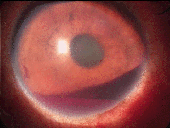

眼外伤引起的前房出血

眼外伤,前房